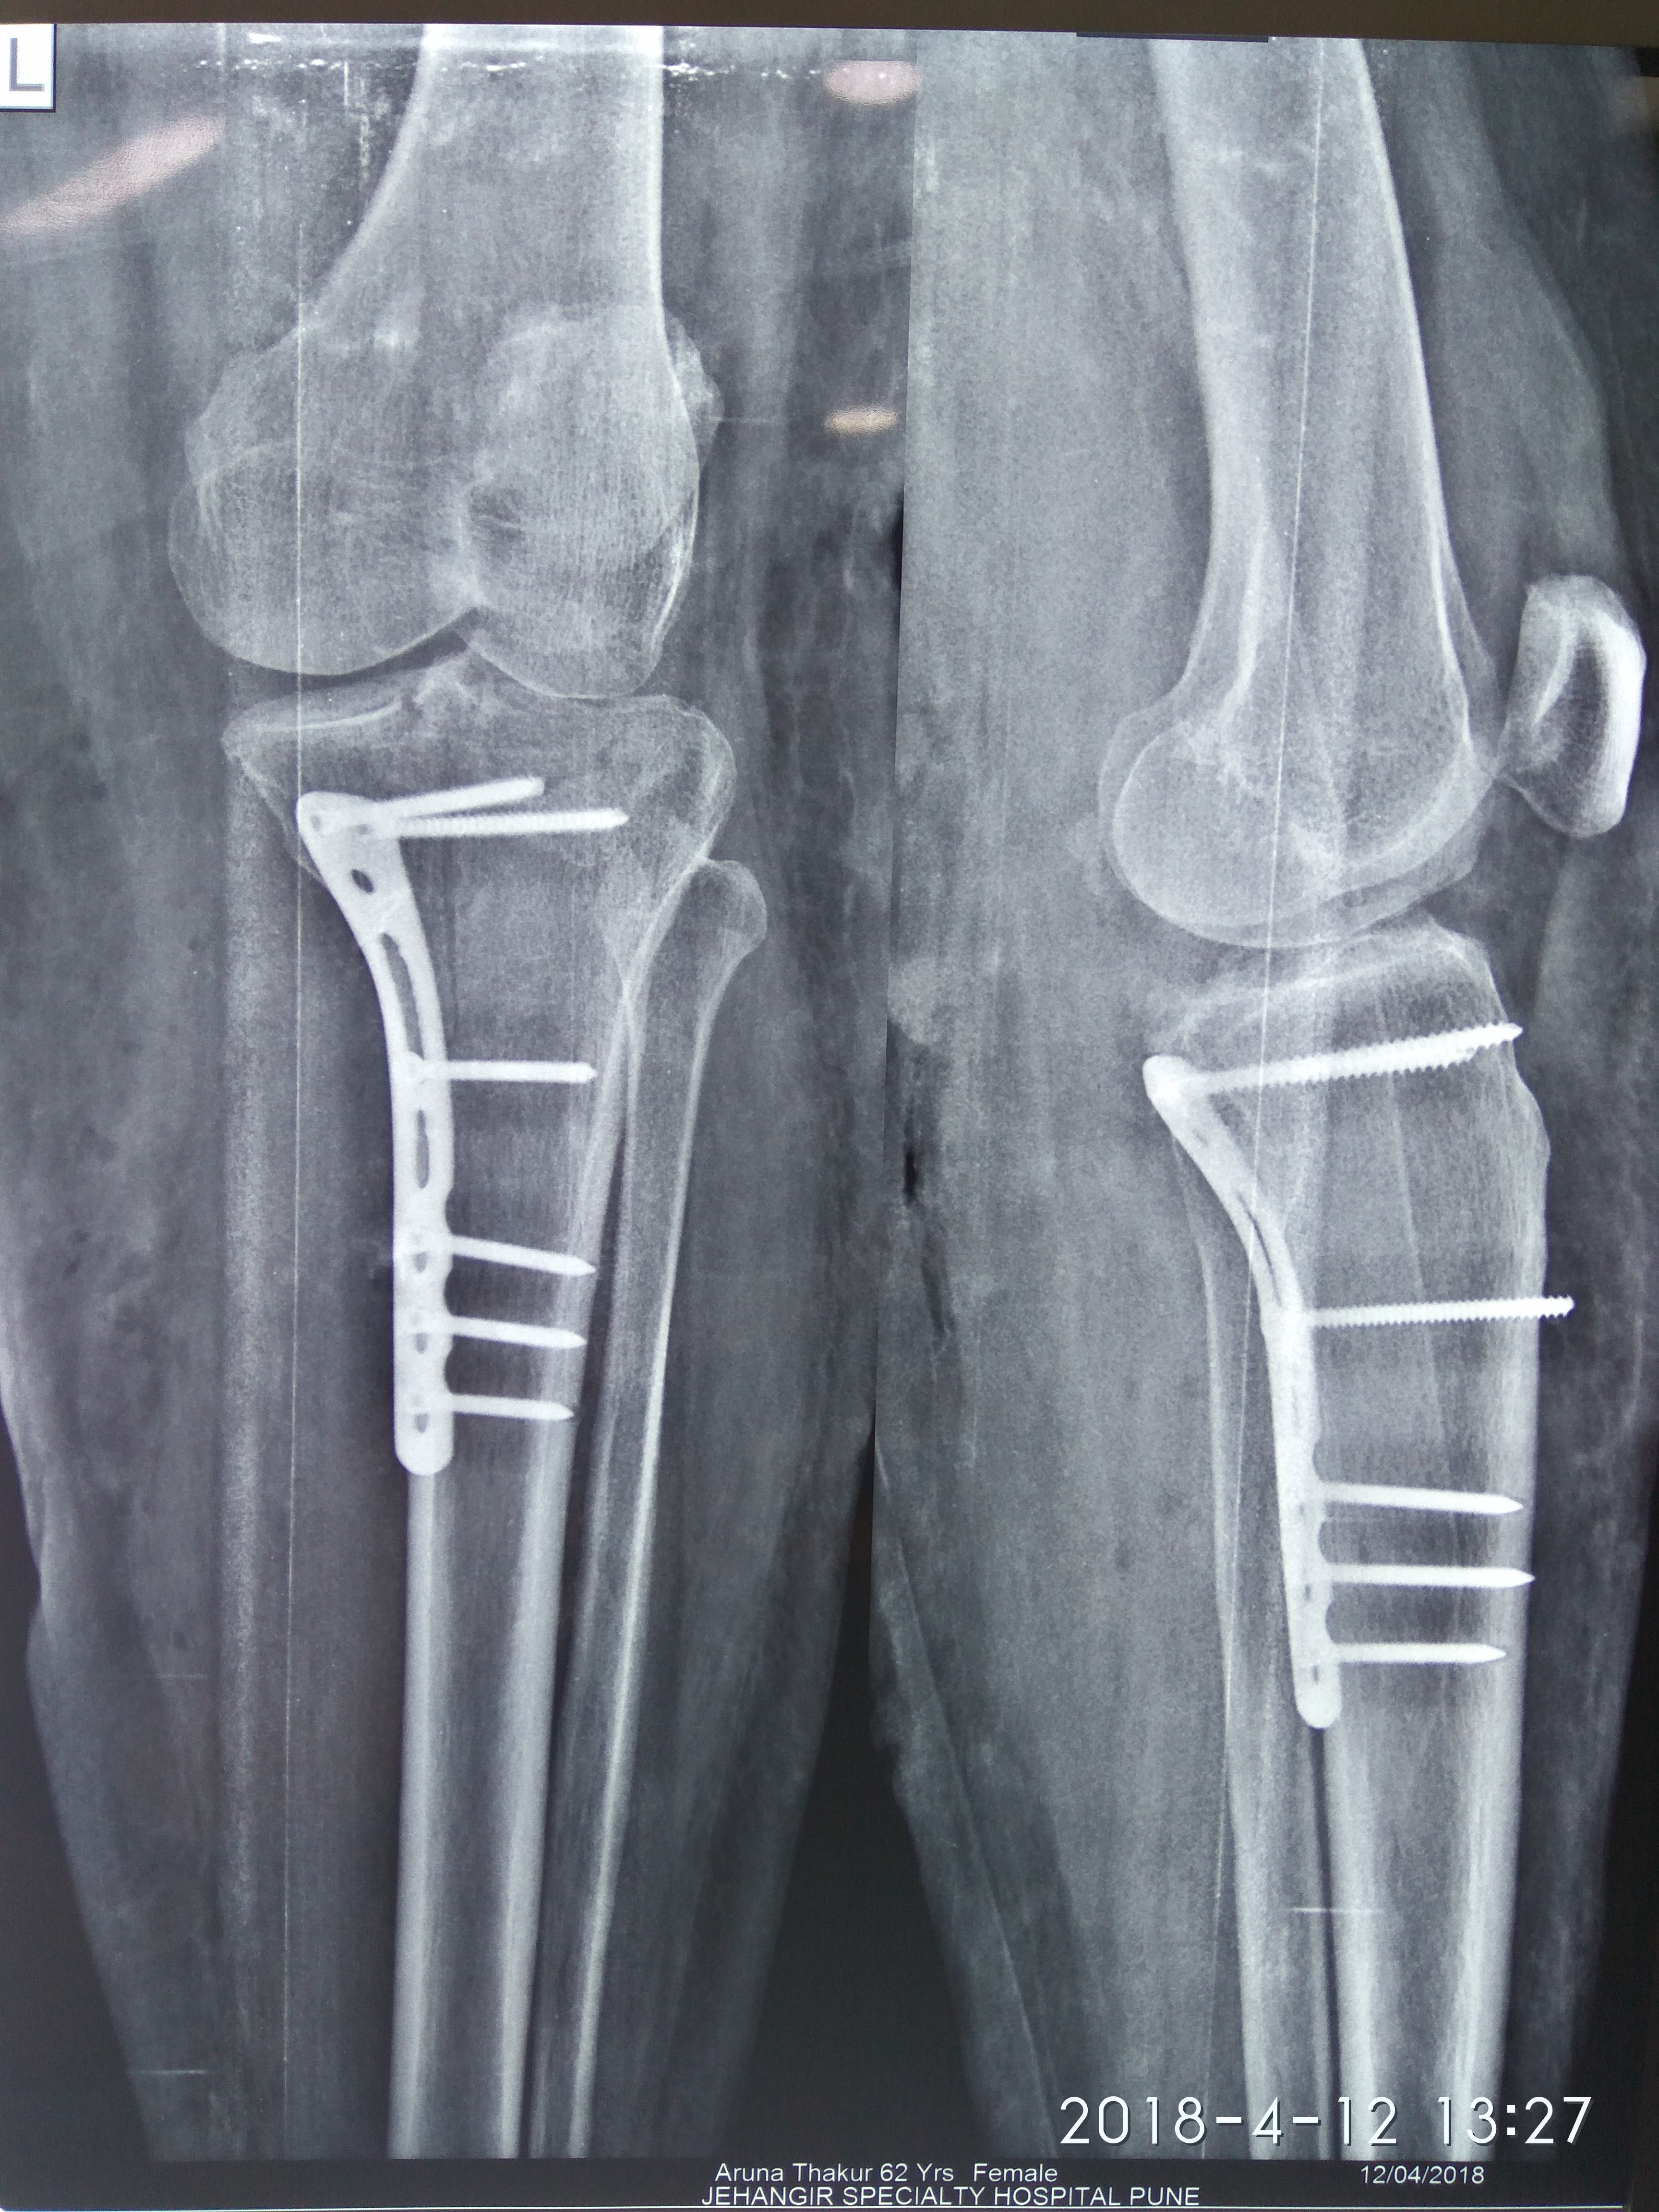

Dr. Sonawane Orthocare clinic is a centrally located Orthopedic Clinic In Pune city near Swargate at Hirabaug Business Centre, Hirabaug chowk, Tilak Road, Shukrawar peth and has easy accessibility from all parts of the city with multiple modes of travelling and enough parking spaces for patients’ own vehicles. Clinic is very modern and stylish and has air conditioned waiting area with comfortable sitting arrangement along with other amenities like TV, Wi-Fi, newspapers. There is hassle-free appointment and consultation system which is totally computerized. Patients get system generated appointment messages, reminders for follow-up dates and prescriptions through messages and emails. So its easy to keep track, keep and carry records and access it anywhere in the world. Clinic offers in-house digital X-ray, pathology tests and physiotherapy facilities at very reasonable rates. This makes the clinic a one stop destination for the patients they don’t need to go anywhere else for these facilities, saving lots of time and effort to get the treatment. We at Dr. Sonawane Orthocare clinic are committed for the best orthopedics care and proud to be one of the best orthopedics clinics in Pune.